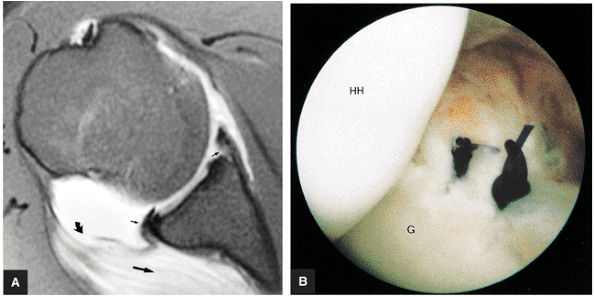

FIGURE 8.102 ● (A) The anterior undersurface of the acromion and the coracoacromial ligament form the coracoacromial arch. The subacromial subdeltoid bursa facilitates the passage of the rotator cuff and proximal humerus under the coracoacromial arch. (B) A superior axial image shows the anterior-to-posterior extent of the coracoacromial (CA) ligament perpendicular to the supraspinatus tendon. The fluid in the subacromial-subdeltoid bursa represents fluid between two serosal surfaces in contact with each other. One serosal surface is contributed by the undersurface of the coracoacromial arch and deltoid, and the other serosal surface is on the bursal side of the cuff.

|

![]() |

FIGURE 8.103 ● Pseudospur. The normal broad attachment of the coracoacromial ligament to the inferior surface of the acromion is shown on (A) T1-weighted coronal oblique and (B) sagittal oblique images. The low-signal-intensity acromial cortex (black arrows) and adjacent coracoacromial ligament and lateral slip of the deltoid attachment (white arrows) give the false impression of a small subacromial spur in the coronal plane. This pseudospur should not be misinterpreted as impingement; otherwise, unnecessary acromioplasties may be performed on patients with a normal coracoacromial ligament attachment and no associated acromial spurs.

-

Impingement syndrome, a clinical diagnosis, is characterized by a range of MR findings from tendinosis to rotator cuff tears.

Intrinsic impingement is associated with shoulder instability.